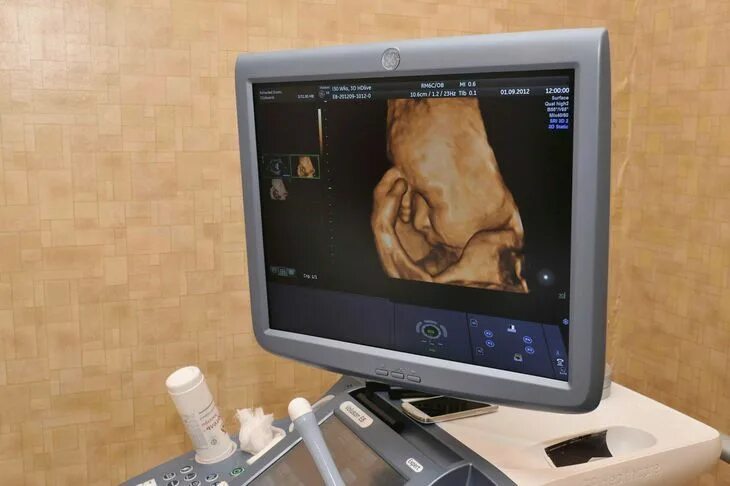

Скрининг 30 недель